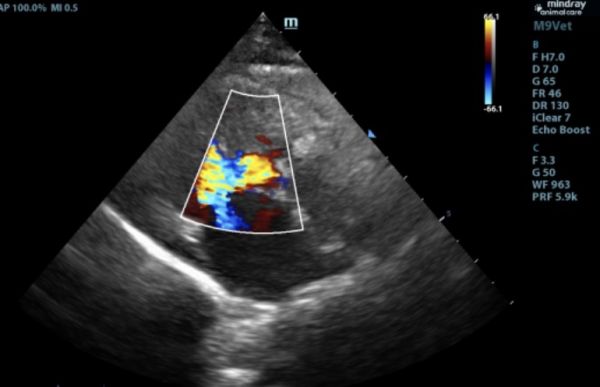

此前,6岁的猫咪因抽搐呕吐,后腿无力就诊,经查后发现左心室心肌及室间隔厚度增加,主动脉和二尖瓣均存在反流,诊断为肥厚型心肌病。口服利尿剂和抗血栓药物,一周后精神好转,再无出现抽搐、呕吐、后腿无力等现象。